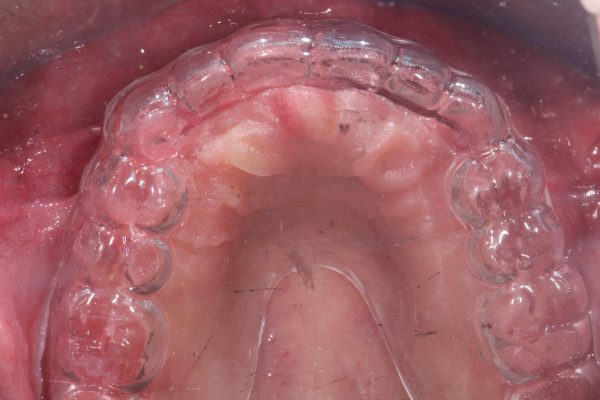

Anche in casi estremamente complessi, la riabilitazione Implanto-protresica , se ben pianificata, può dare dei risultati soddisfacenti, sia dal punto di vista estetico che funzionale.Scopri di più